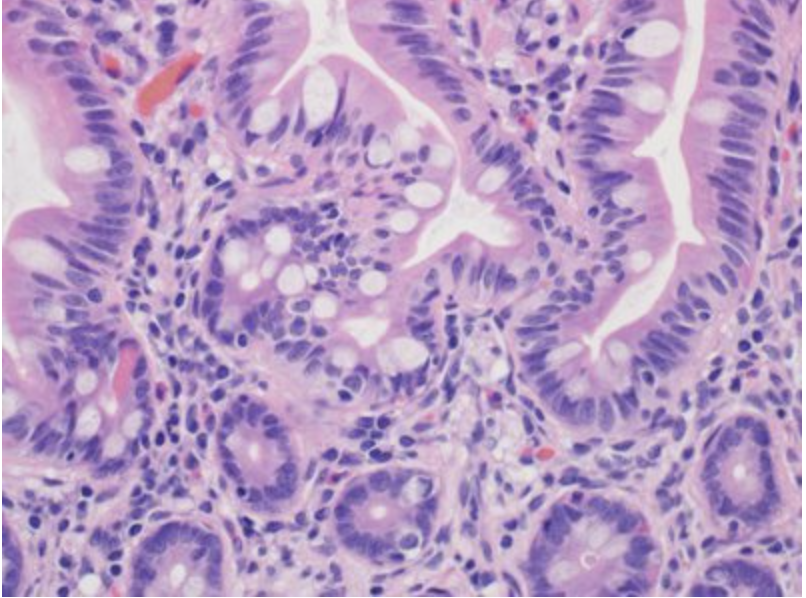

In this image, identify the lamina propria!

The conective tissue that underlies the epithelia lining the organs of the digestive, respiratory and urinary systems is called lamina propria